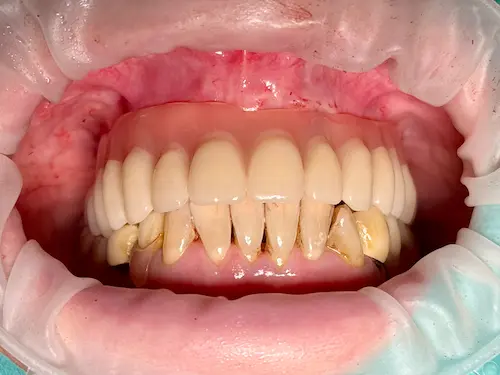

Der chirurgische Eingriff im Detail

Der Tag der Operation ist gekommen: Im ersten Schritt werden die noch vorhandenen Zähne gezogen sowie die Wurzeln und vereinzelte Zysten restlos entfernt. Dies erwies sich im vorliegenden Fall als extrem komplex und folgenreich: Beim Extrahieren gingen Teile der Knochenwände verloren, was einen deutlichen Mehraufwand beim Aufbau des Kieferkamms nach sich zog. Zuzüglich zu Knochenersatzmaterial verwendete Dr. Mintert dafür 2 Collagen Blöcke, 2 Membranen und 0,3 ml Emdogain. Letzteres dient der Entwicklung von zahnstützendem Gewebe. Auch Eigenknochen aus einem zweiten OP-Gebiet kam zum Einsatz. Im Oberkiefer wurde außerdem ein sogenannter Sinuslift durchgeführt, der – vereinfacht gesprochen – die Kieferhöhlen anheben soll. Nun waren die Grundlagen für den nächsten Schritt geschaffen: Eine eigens angefertigte Bohrschablone ermöglicht die navigierte Implantation. So fanden alle acht Implantate trotz ungeplanter Komplikationen ihren rechten Platz im Mundraum. Abschließend wird L-PRF Plasma, d.h. zentrifugiertes Eigenblut eingebracht, um die Wundheilung zu unterstützen. Als Zahnersatz werden zwei festsitzende Keramikbrücken gewählt und auf künstliche Keramikaufbauten geklebt. Diese wiederum sind mit jeweils vier Implantaten verschraubt.

Röntgenaufnahme - nach OP - All-on-Four

All-on-Four Zahnersatz nach OP - Patientenansicht